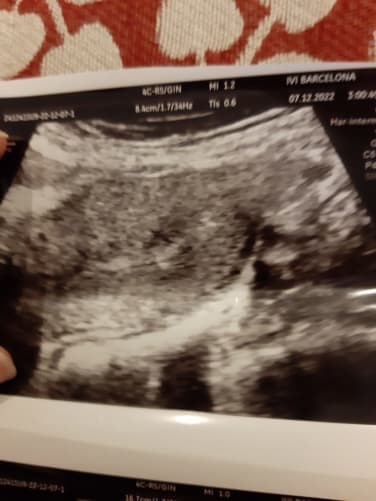

Départ 31 novembre 2022, pour l’Espagne, on arrive le 1er et premier rdv, le lendemain je fais mon don de sperme, 5 jours après on nous annonce que 12 embryons ont été fécondés, mais que 9 son viables, au final on aura 4 embryons congelés les plus résistants, les autres seront utiliser pour analyses. Le jour du transfert arrive et tout se passe très bien. En 2 h c’est fait.